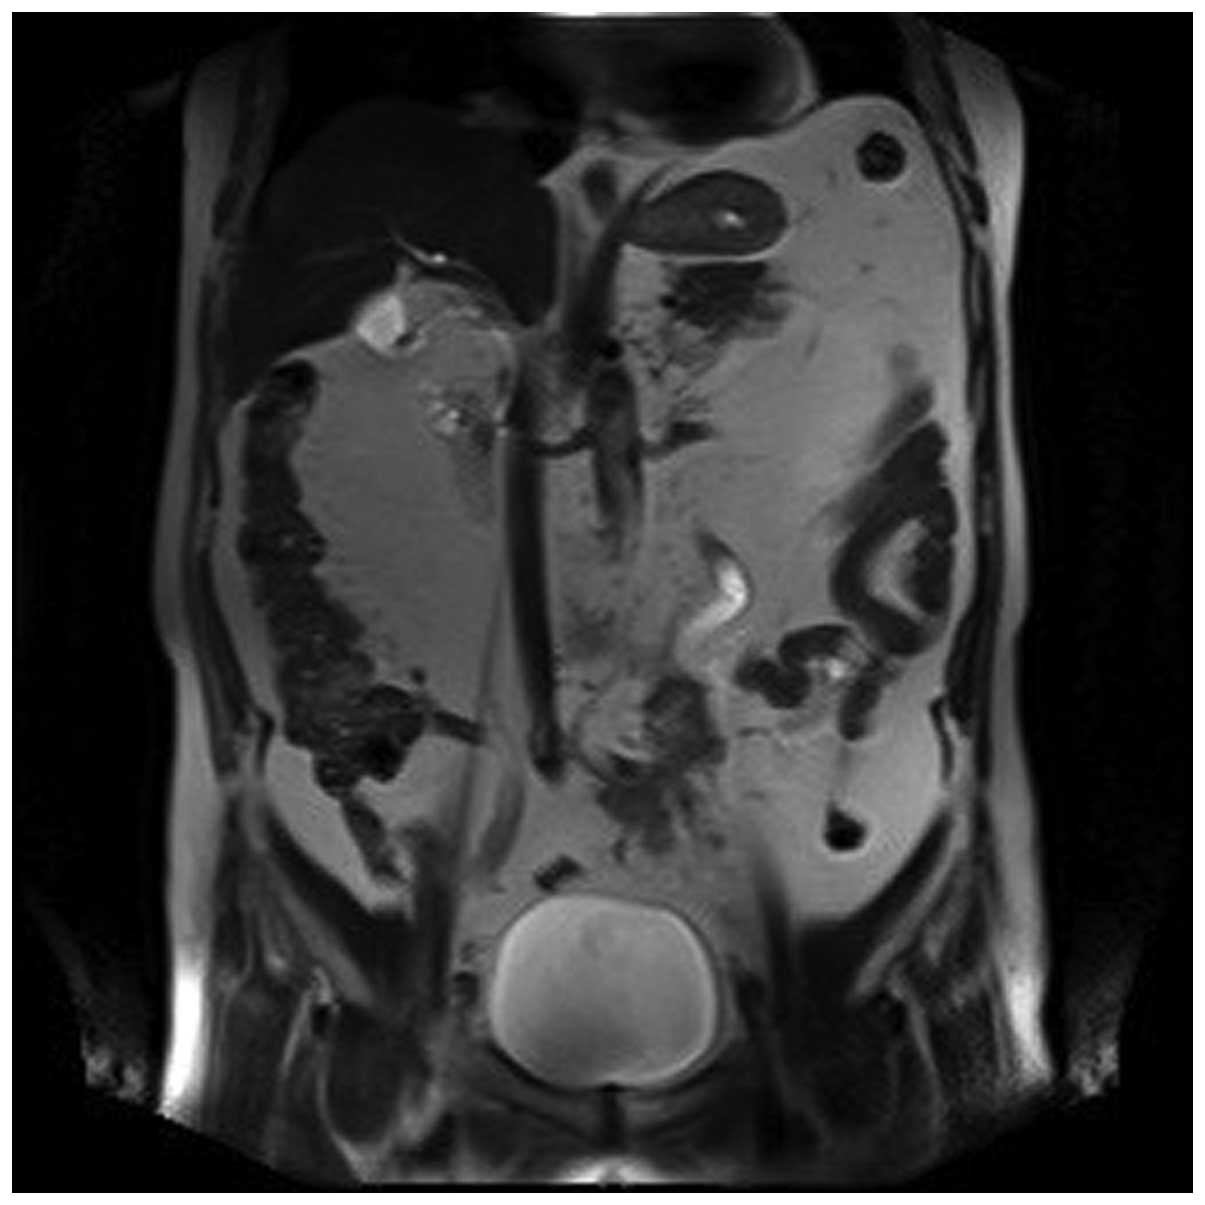

A 69-year-old Chinese Han male patient was admitted to the Department of Urology of Tianjin First Central Hospital (Tianjin, China) with a 10-month history of gross hematuria and 1-month history of left flank pain. The medical history of the patient included 17 years of hypertension, 20 years of coronary heart disease and an allergy to iodine. The findings of the physical examination were normal. The findings of the routine laboratory examinations were unremarkable. However, on urinalysis, there was macroscopic hematuria and 40–50 white blood cells per high-power field. On magnetic resonance imaging of the urinary tract, the iliac wing level around the left ureter exhibited an iso-intense T2 signal, an irregular mass with a rough outline and unclear boundaries of the corresponding level of the left iliac vessels. There was occlusion of the left ureter at the corresponding level, with hydronephroureterosis above the mass and undevelopment of the segment of the left ureter below the mass (Figs. 1, 2 and 3). The right kidney was normal. Chest radiographs were performed and revealed no primary or metastatic lung lesions. Left nephroureterectomy was performed and the clinical diagnosis was primary ureteral tumor. The gross examination revealed an ovoid, solid, white mass, sized 3.5×3.0×1.6 cm, originating from the ureteral mucosa and protruding into the ureteral lumen, with invasion of the periureteral adipose tissue. Examination under a light microscope revealed that the tumor was composed of atypical carcinoid cells with diverse shapes, with common mitotic figures, and small cells with a round to fusiform shape, scant cytoplasm, fine granular nuclear chromatin, and absent or inconspicuous nucleoli (Fig. 4). The tumor cells exhibited cytoplasmic positivity for cytokeratin (CK)7, epithelial membrane antigen (EMA), CD56 and synaptophysin, and negativity for neuron-specific enolase (NSE), chromogranin A (CgA) and CK20. The Ki-67/MIB1 index was 20%. The patient was diagnosed with NEC of the ureter with atypical carcinoid and small-cell carcinoma components. The postoperative recovery of the patient was uncomplicated; however the patient refused chemotherapy or radiotherapy. During the regular follow-up examinations, there was no evidence of tumor recurrence at 5 months postoperatively; however, he succumbed to extensive metastases after 12 months of follow-up.

Figure 3.

The segment of the left ureter below the mass was undeveloped.